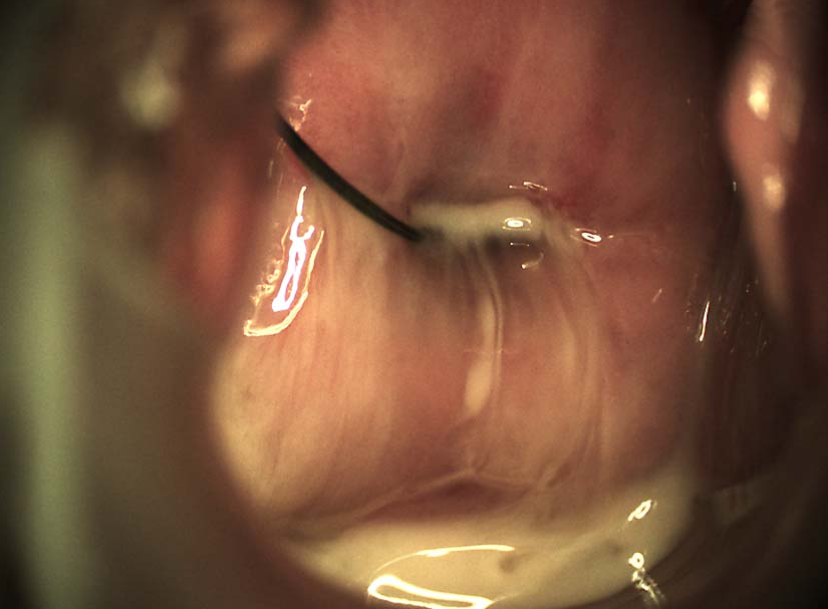

肝周围炎腹腔镜所见,可见琴弦样粘连改变